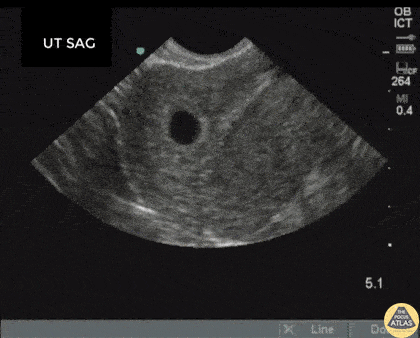

OB/Gyn - IUD Foreign Body

Transvaginal US showing a gestational sac of about 6 weeks by dates with a fragment of an old IUD embedded in the endometrium shown as the hyperechoic line with posterior acoustic shadow. Patient had an IUD removal 10 months prior. Image courtesy of Robert Jones DO, FACEP @RJonesSonoEM Director, Emergency Ultrasound; MetroHealth Medical Center; Professor, Case Western Reserve Medical School, Cleveland, OH View his original post here